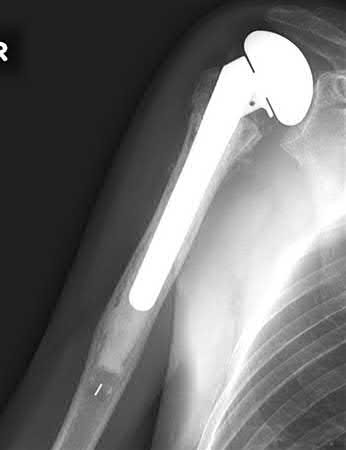

A 64-year-old woman is thrown off a horse, sustaining the injury shown in Figures A and B. She undergoes surgical fixation as seen in Figures C through E. What is the most commonly reported complication of this procedure?

The patient in the scenario has a 2-part proximal humerus fracture treated with a locking plate as seen in Figures A-E. The most common complication with the use of this implant is screw penetration. The terms screw cut out and penetration are often used interchangeably in the literature with cut out appearing more frequently in reports regarding intertrochanteric fractures.

Owsley et al retrospectively reviewed 53 proximal humerus fractures treated with locking plates and the same post-operative protocol. The most common complication was screw cut out or penetration, followed by varus displacement. They concluded that 3 and 4-part fractures in patients over 60 years have a higher incidence of failure.

Agudelo et al retrospectively reviewed 153 patients at a level-one trauma center treated with proximal humerus locking plates, investigating modes of failure for the implant. They determined that varus malreduction (head-shaft angle